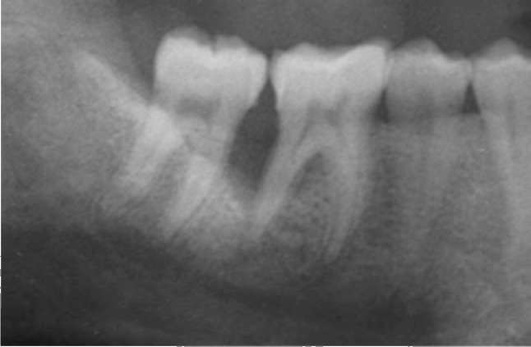

Этиология и патогенез. Важную роль в развитии пародонтита играют усиление повреждающего действия микробных скоплений десенной бороздки по мере как простого увеличения количества микробных масс, так и увеличения в их составе наиболее патогенных форм. Однако для реализации их разрушающего потенциала недостаточно только перечисленных изменений микробного состава. Необходимы снижение резистентности организма, неблагоприятное воздействие на пародонт нервно-соматических заболеваний, нарушения обмена и т.д. (рис. 14-20).

image

Рис. 14-20. Современная концептуальная модель пародонтита (Kornman K.S., 2008): ПМЯЛ - полиморфно-ядерные лейкоциты; ЛПС - липополисахариды; ММП - матриксные металлопротеиназы